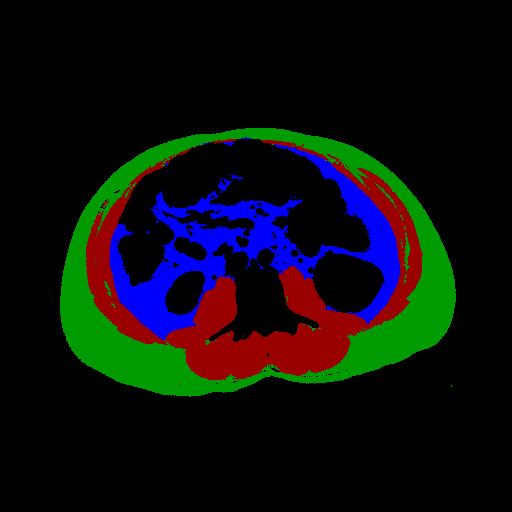

The full validation was then performed on Dataset B treating the two models as a single process that takes in a full abdominal CT series and produces estimates of body composition in terms of square cross-sectional area of muscle, subcutaneous fat, and visceral fat. In this case, the DSC is not an appropriate measure because the segmentation may be performed on a different slice from the ground truth mask. Table 2 compares the accuracy of the different tissue types and Figure 3 shows some example outputs.